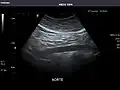

Aorta: Visualized portions normal in caliber, 16 x 15 mm.

Aorta -

It can be used on the abdominal aorta to detect or exclude abdominal aortic aneurysm. For this purpose, the standard aortic measurement for abdominal aortic aneurysm is between the outer margins of the aortic wall.[4]